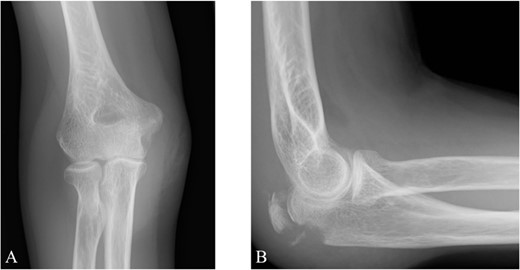

The surgery was performed in the left lateral recumbent position. An incision was made in the posterior midline over the right olecranon. Triceps brachii tendon rupture was not observed (Fig. 2). The fracture fragment was inverted, and two 1.4-mm JuggerKnot® All-Suture Anchors (Zimmer Biomet, USA) were inserted into the ulna proximal to the fracture site without perforation into the elbow joint. Subsequently, sutures were threaded through the triceps brachii muscle; the dislocated bone fragment was pulled together with the triceps brachii muscle. Despite maintaining the elbow at a 30° flexion position, two Quattro® Link Knotless anchors (Zimmer Biomet, USA) were inserted into the ulna distal to the fracture site to reduce and fix the fragment using the suture bridge procedure (Fig. 3). However, upon flexing the elbow joint to 90°, the bone fragment was displaced and anchors were loose. Therefore, we opted to use the McLaughlin cerclage technique, utilizing a 2.3-mm BroadBand® Tape (Zimmer Biomet, USA) passing through a predrilled hole perpendicular to the ulnar shaft. The suture was crossed over the posterior aspect of the ulna and tightened in a figure-of-eight manner through the triceps brachii tendon (Fig. 4). This procedure resulted in no dislocation of the fracture site, even when the elbow joint was flexed to 130°.

The bone fragment is displaced, and its continuity with the triceps tendon is preserved.